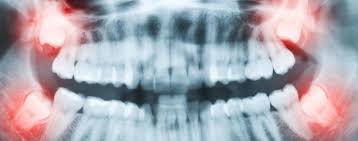

Eine Entzündung des Weisheitszahns ist sehr schmerzhaft und äußert sich daneben häufig mit Rötung Schwellung und Eiterbildung. In den ersten Monaten hatte ich ein Taubheitsgefühl in der Unterlippe das nach längerer Zeit verschwand. Der Weisheitszahn links unten entfernt der letzte endlich.

Häufig verläuft ein Nerv entweder durch die Wurzeln oder am Zahn entlang. Und bei nicht wenigen war es der fall dass der eingriff nah am nerv vorgenommen wurde das risiko also da war. Bevor ich meinen körper über jahre mit schmerzmitteln schädige und schmerzen leide würde ich mich diesem eingriff unterziehen.

Sie liegen sehr nah am Nerv weshalb der Arzt nur zwei auf Einmal zieht. Bei der lokalen Narkose besteht das Risiko vor allem dadurch dass durch die Nadel ein Nerv beschädigt wird.